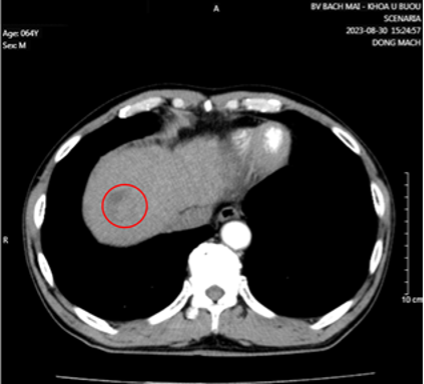

Cắt lớp vi tính ổ bụng có tiêm thuốc cản quang:

Hình 3: Nhu mô hạ phân thùy VII có vài khối, nốt kích thước lớn nhất 33x26mm giảm tỷ trọng trước tiêm, ngấm thuốc thì động mạch (vòng tròn đỏ), thải thuốc thì tĩnh mạch cửa (vòng tròn).